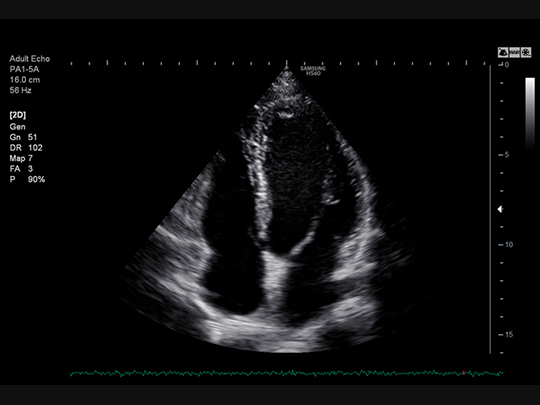

Samsung HS60 Compatible Transducers / Probes

Phased array transducers

PA1-5A

- Application: abdomen, cardiac, vascular